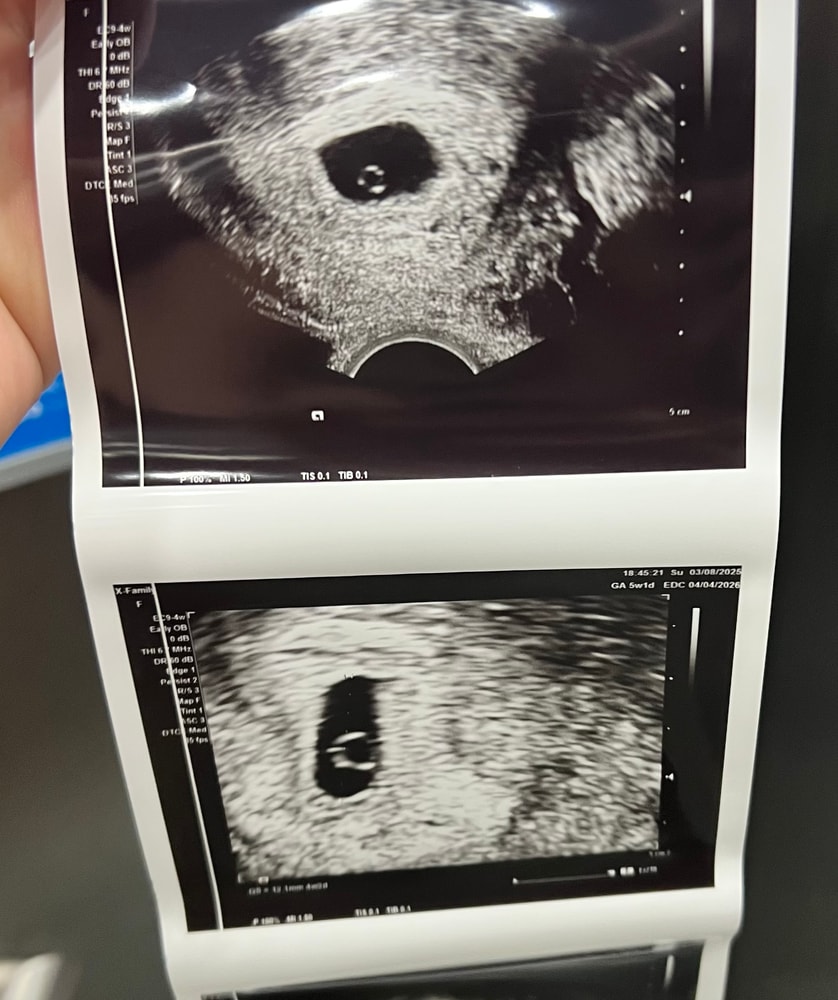

Нашла желточный мешочек))

Сидеть и спокойно ждать две недели я не смогла, моя тревожность погнала меня палкой делать ТВУЗИ и искать жм. Узистка попалась мега странная, пыталась найти сердце в 5+1 и даже включила допплер на пару секунд, я там аж подлетела. Замеры тоже делать не стала, но главное, я увидела СВОЙ МЕШОК. Все хорошо, теперь я действительно наконец успокаиваюсь и жду узи с сердечком 🙏 Эта беременность испытывает мою веру и терпение, начинается с небеременного хгч спустя целый день полосок, затем хгч не удваивается, затем мне не находят жм в 5+0 и говорят, что никаких 5 недель у меня там и нет вовсе. Короче мораль пока что верить в малыша вопреки неидеальным цифрам.

фоточка мешков: